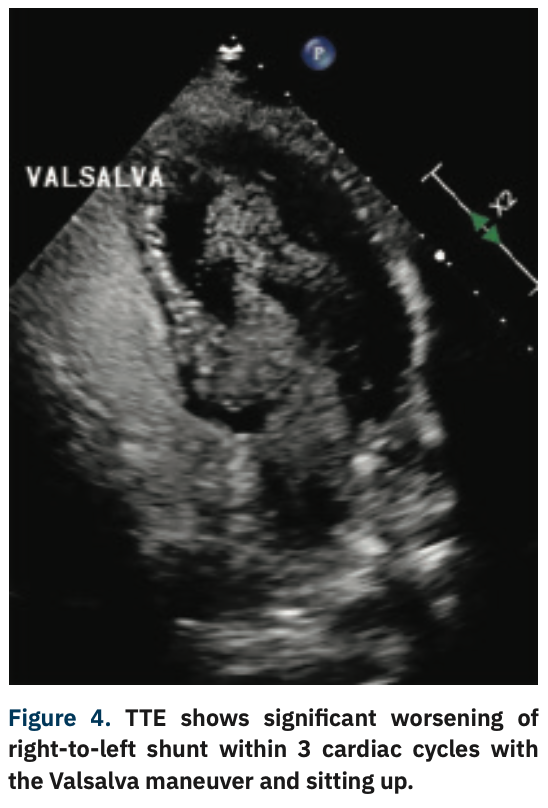

He was admitted with diagnosis of acute hypoxic respiratory failure secondary to a presumptive diagnosis of hypersensitivity pneumonitis given his history and was started on intravenous steroids. Despite treatment, he continued to get progressively hypoxemic, requiring high-flow O2. After an extensive and detailed pulmonary workup at the outside facility, he was transferred to our facility for further evaluation and management. Repeat echocardiography demonstrated a large PFO using agitated saline. A subsequent transesophageal echocardiogram (TEE) revealed normal biventricular size and function, an atrial septal aneurysm (Figure 1), and color-flow Doppler suggested the presence of a PFO with predominant right-to-left shunting (Figure 2). Right heart catheterization demonstrated normal central filling pressures with no evidence of left-to-right shunting.